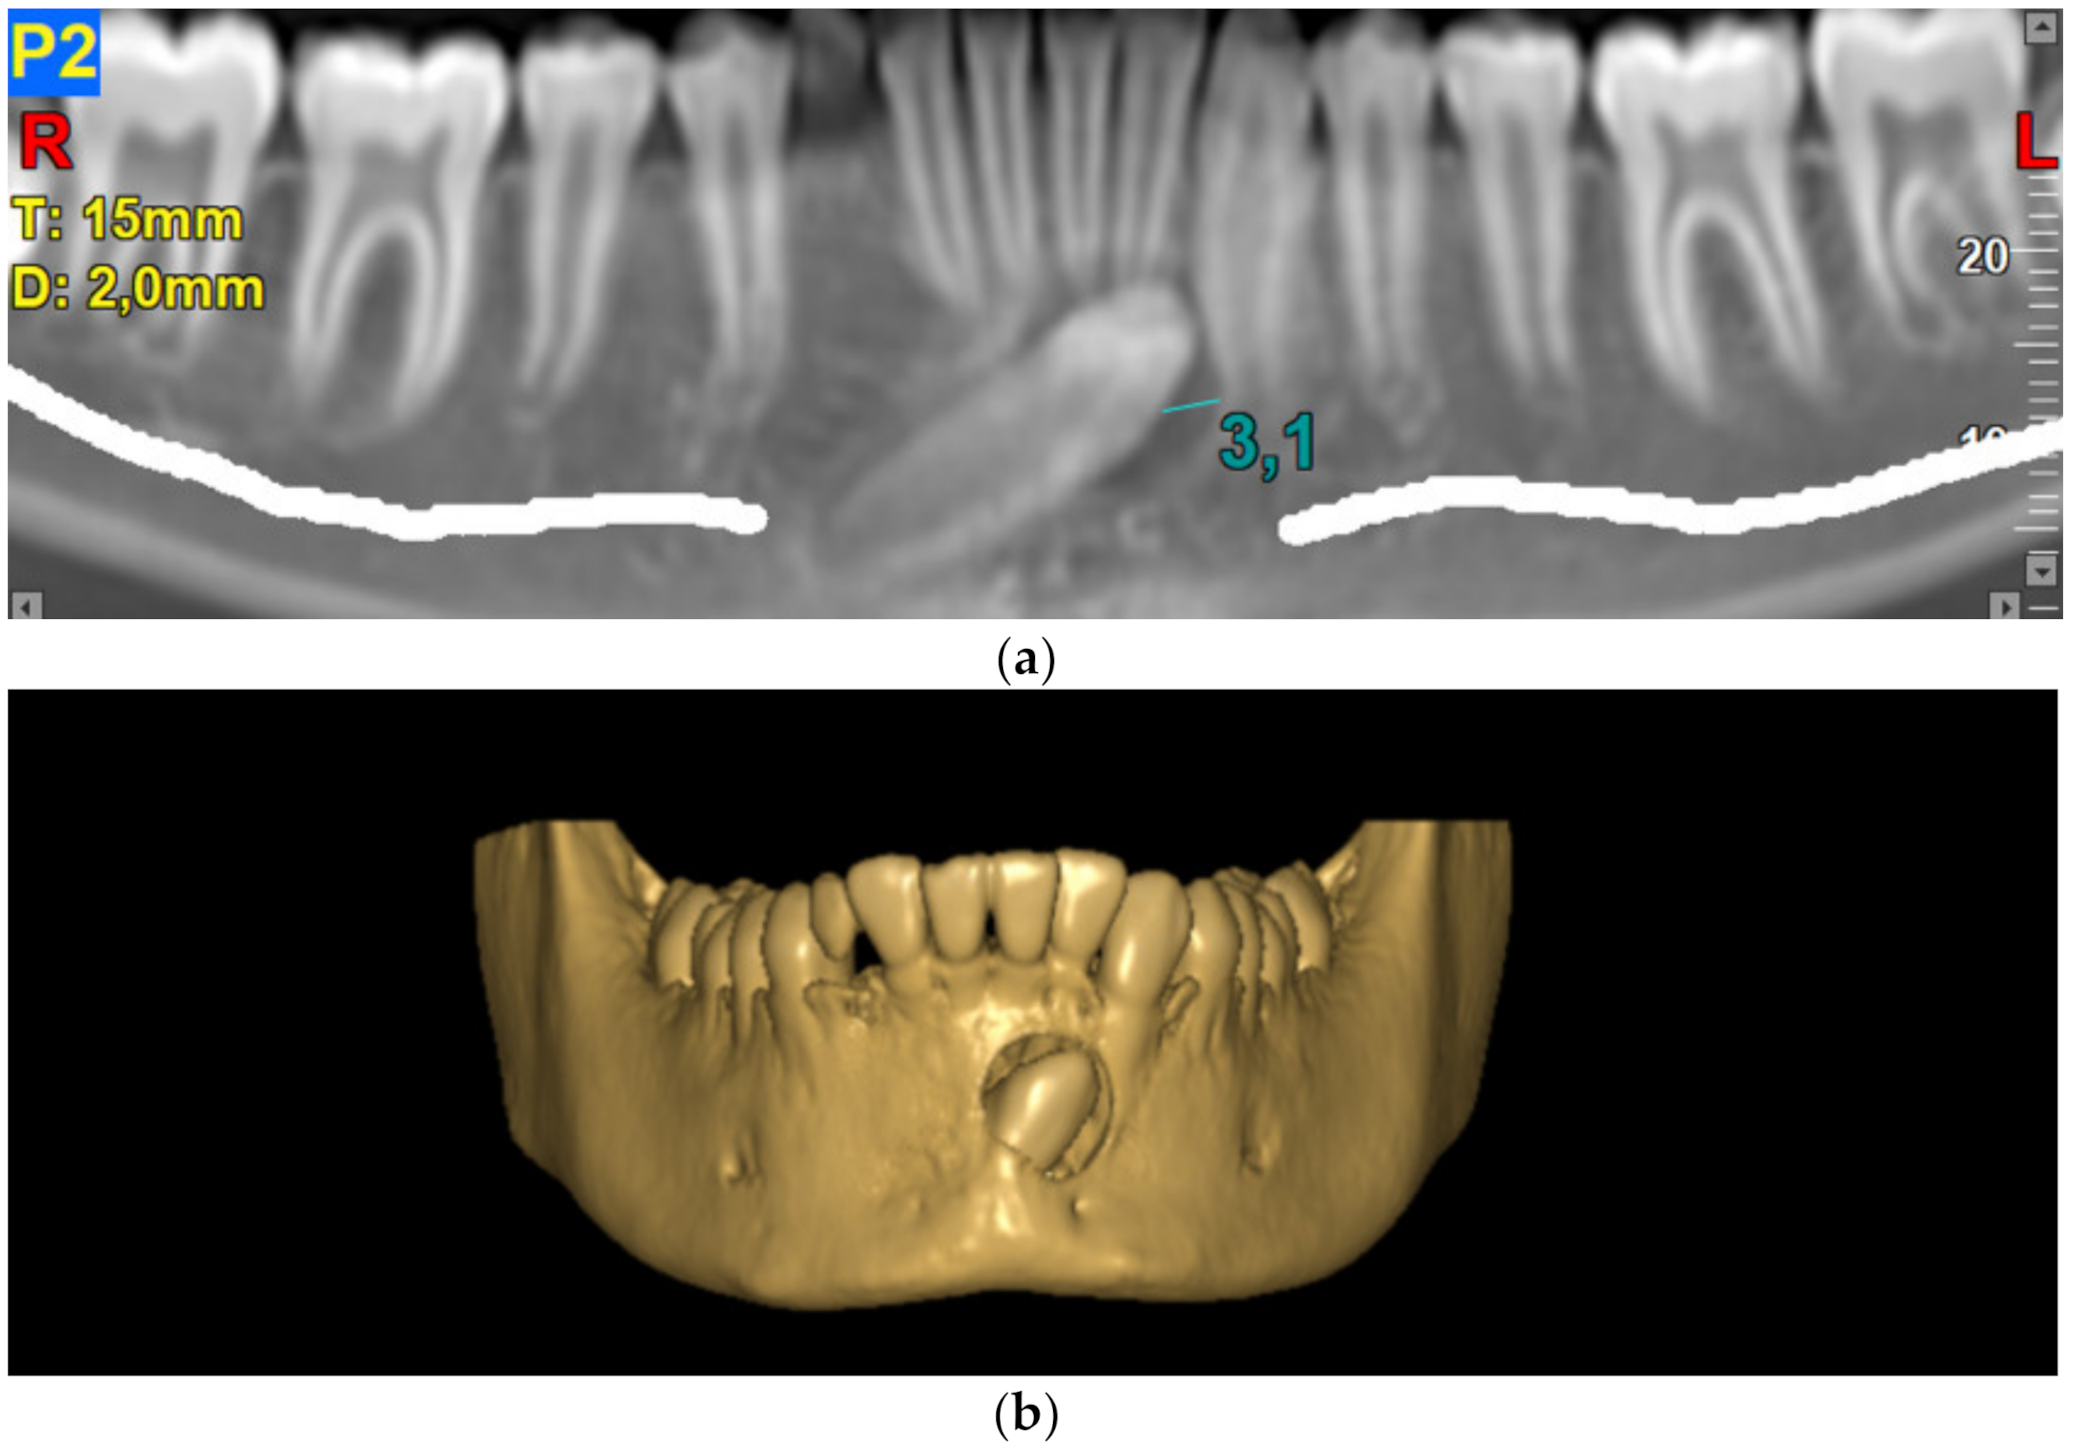

- Vaida, L.; Todor, B.I.; Corega, C.; Băciuţ, M.; Băciuţ, G. A rare case of canine anomaly—A possible algorithm for treating it. Romanian J. Morphol. Embryol. 2014, 55, 1197–1202. [Google Scholar]

- Gruszka, K.; Różyło, T.K.; Różyło-Kalinowska, I.; Denkiewicz, K.; Masłowska, K. Transmigration of mandibular canine—Case report. Pol. J. Radiol. 2014, 79, 20–23. [Google Scholar] [CrossRef] [PubMed]